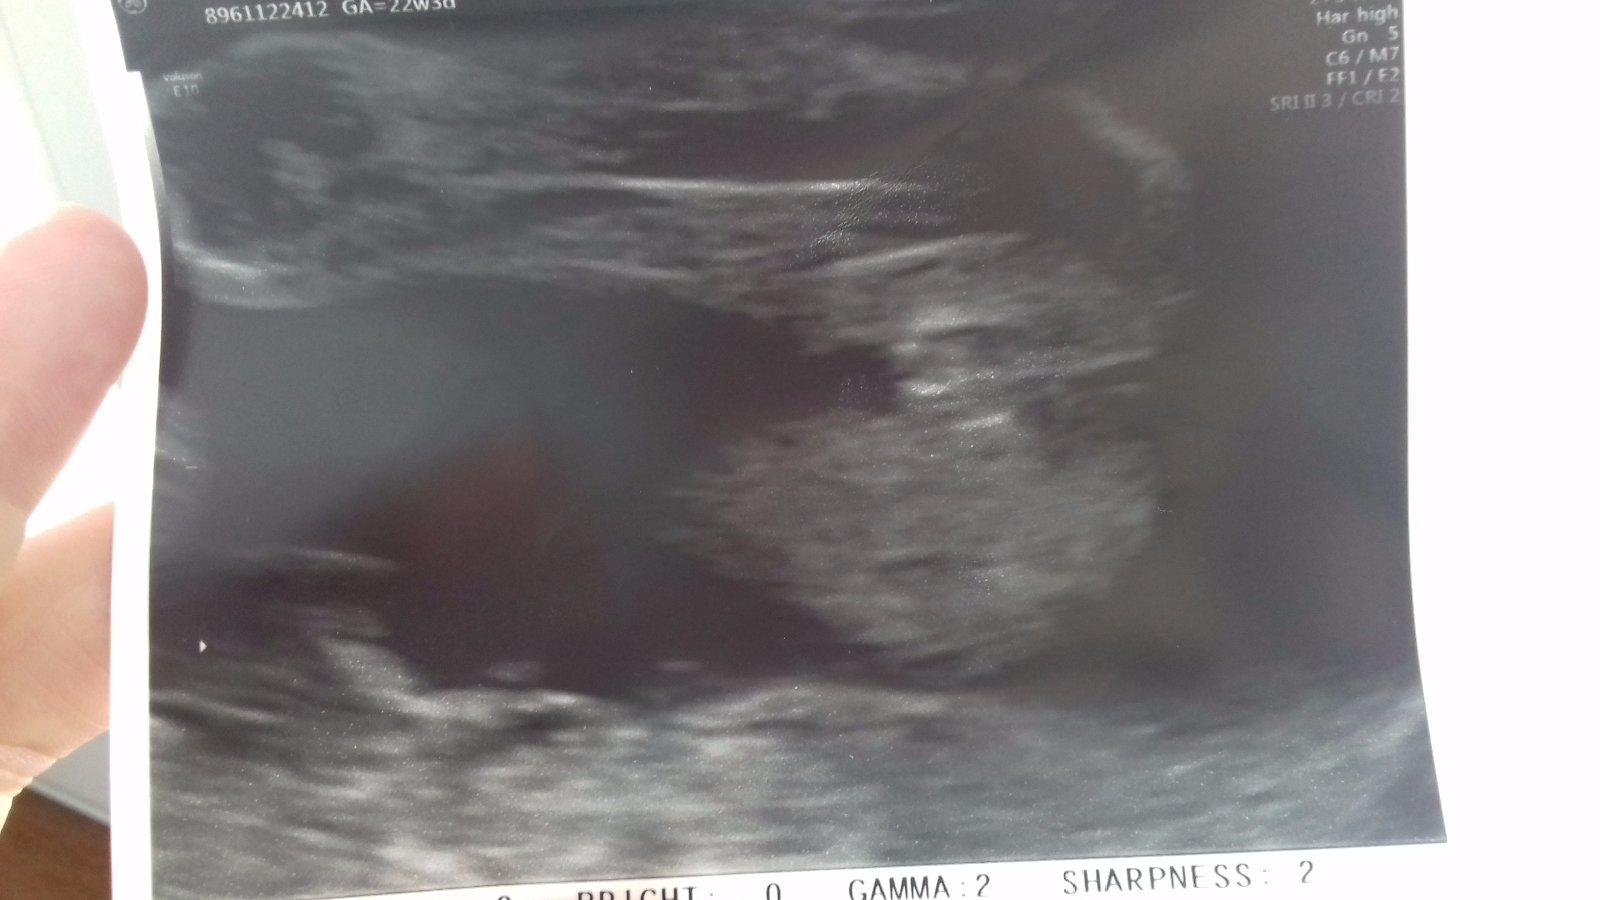

Ahoj maminky, co myslite? Holka nebo kluk? 😊

Nejsem odborník, ale podle mě holka. 🙂 Já tam vidím kávové zrno 🙂

mam podobnou fotku a mam doma 10mes.holcicku ,takze si myslim ze holka

vypadá to na holku 🙂 gratuluju